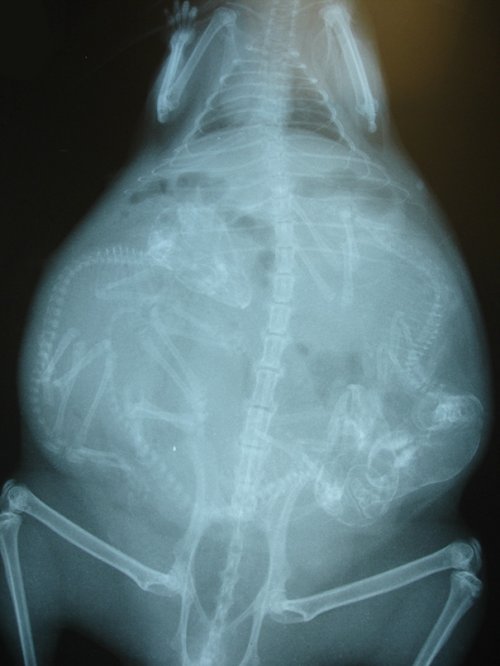

Итак, как выглядят рентгеновские снимки беременных животных:

морская свинка